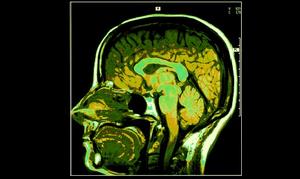

印度最高法院的這項判決剝奪了警方以及調查員歷來經常使用的一個工具。印度首席法官巴拉克里斯南(K G Balakrishnan)表示,讓嫌犯使用靜脈麻醉劑硫噴妥鈉後進行問話的行為是違反憲法的,任何嫌疑都不應該被迫成為一個對自己不利的證人,以後測謊儀和大腦映射(brain mapping)法也都被視為非法行為。